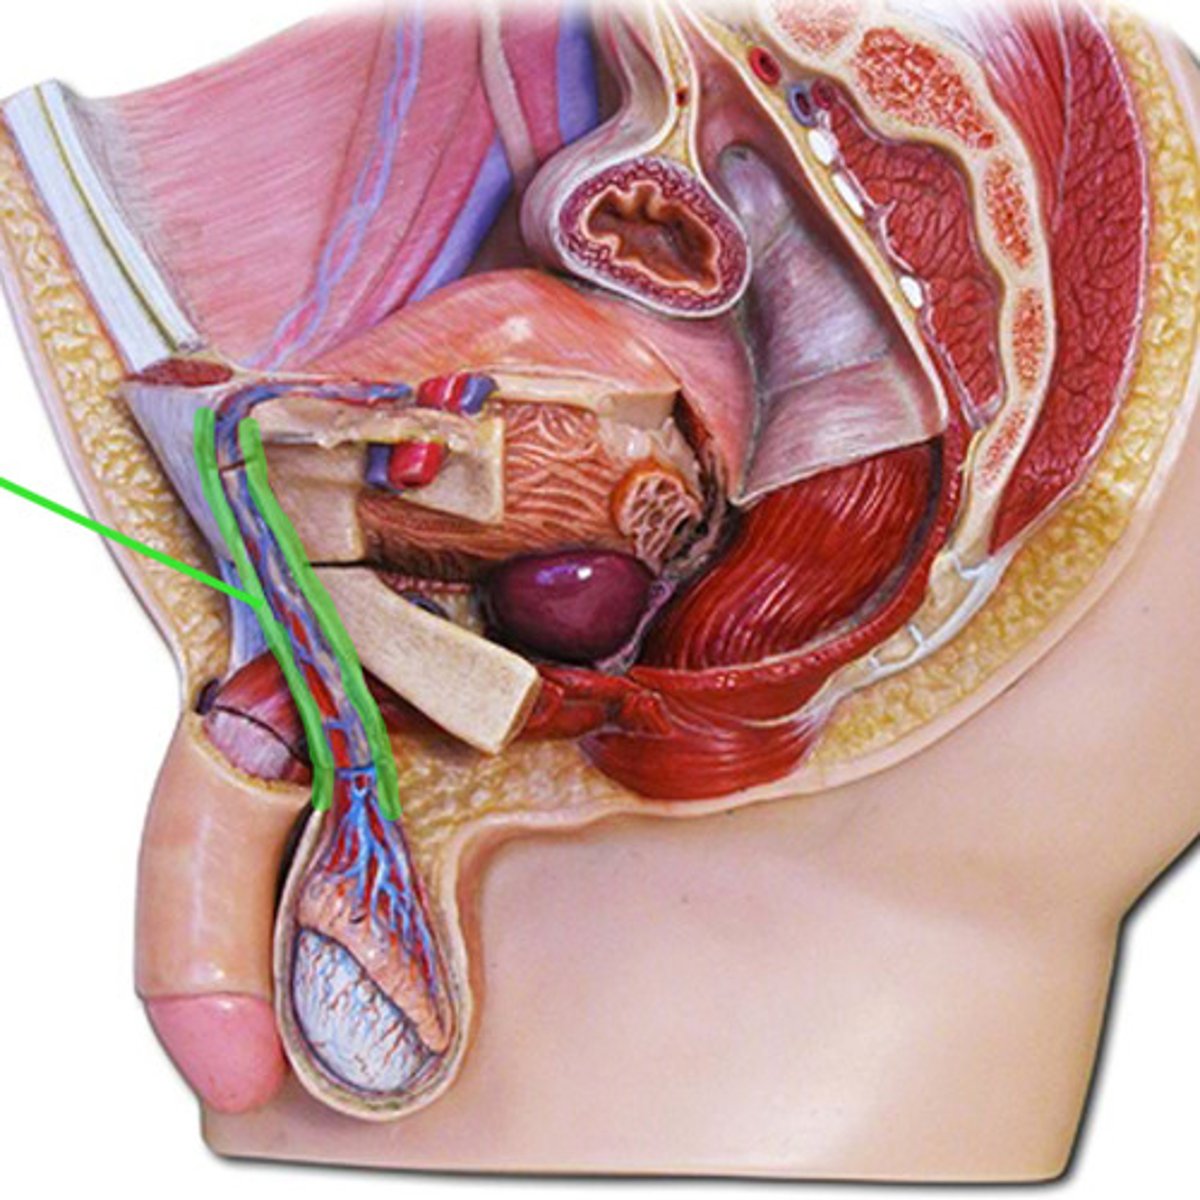

Spermatic cord

Ductus deferens

Ampulla (ductus deferens)

Ejaculatory duct

Seminal gland

Prostate gland

Bulbourethral gland

Urethra

Urethra

Prostatic urethra

Membranous urethra

Spongy urethra

Penis